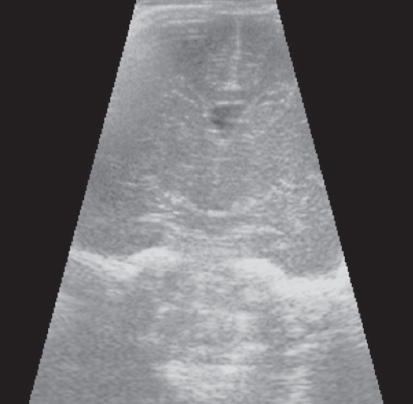

At the PCA of 30 weeks, the thickness of the germinal matrix could not be determined using CUS. An ultrasonographic image of the brain in a premature infant at the PCA above30 weeks showed lack of a visible germinal matrix in the anterior horn of lateral ventricles (Fig. 3).

Fig. 3. CUS image of preterm newborn, gestational age 30 weeks, frontal scan. The germinal matrix is not visualized

Рис. 3. Краниальная сонография недоношенного ребенка 30 недель ПКВ. Фронтальный скан. Герминальный матрикс в просветах передних отделов боковых желудочков не визуализируется